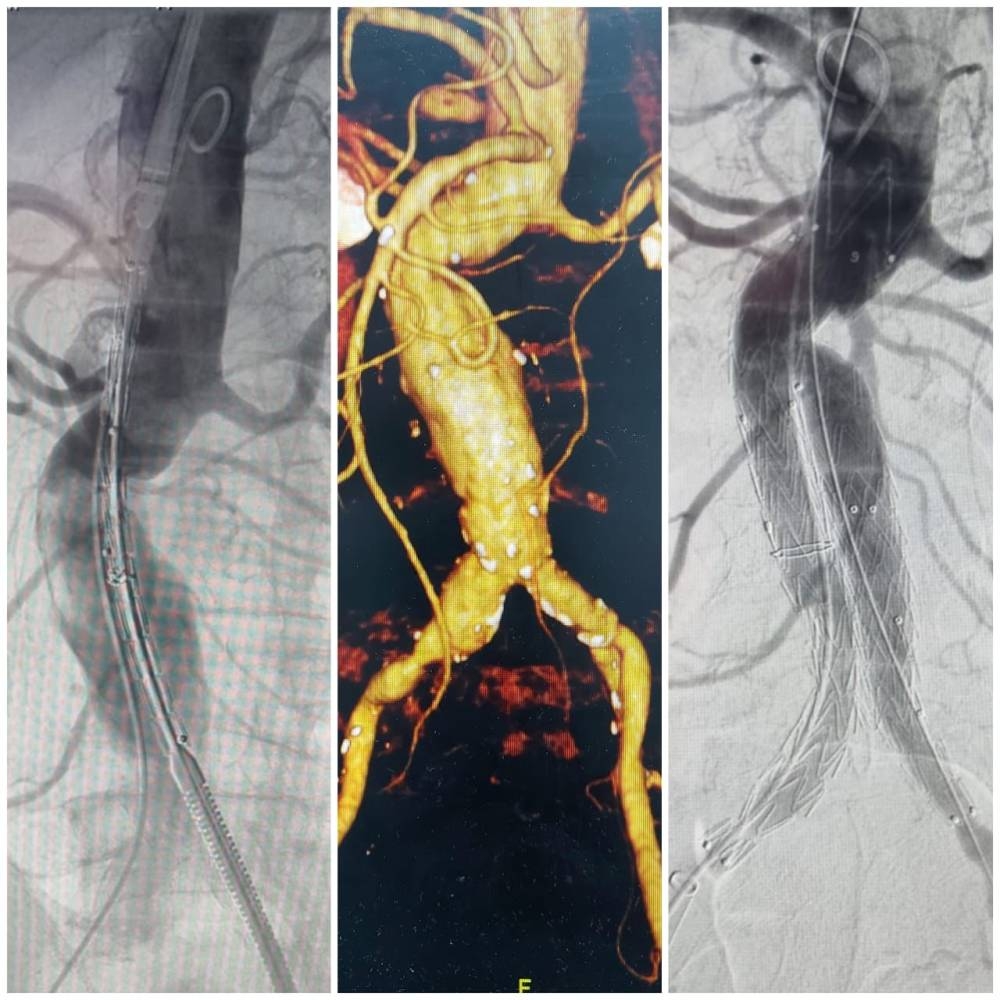

وأشار الفريق الطبي المشرف على الحالة إلى أنه وبعد إجراء الفحوصات السريرية والمخبرية والإشعاعية العاجلة تأكد أن المريض لدية تمدد كبير بالشريان الأورطي بالبطن والشرايين الحرقفية بمنطقة الحوض، الأمر الذي تسبب بالضغط على الفقرات القطنية للمريض محدثاً هذه الآلام، حيث تم تقديم الخدمات العلاجية الطارئة التي أسهمت في السيطرة على الوضع الصحي للمريض ليتم على الفور تركيب دعامة مغطاة بالشريان الأورطي وشرايين الحوض عن طريق قسطرة الأوعية التداخلية تحت تأثير المخدر الكلي.

وبين الفريق المعالج أنه وبعد رجوع العلامات الحيوية لوضعها الطبيعي تم إحالة المريض إلى قسم العناية المركزة لمتابعة وضعه الصحي من قبل الأطباء وفرق التمريض وتقديم العلاجات المناسبة التي تسهم بإذن الله من تحسن الحالة وخروجها من المستشفى خلال الفترة القادمة.

وعدّ الفريق الطبي المعالج هذا النوع من العمليات التي تعالج الشريان الأورطي من أكبر العمليات في مجال جراحات الأوعية الدموية، حيث إن الشريان الأورطي هو الشريان الرئيسي بالجسم وتمدد الشريان لدرجة معينة قد يؤدي إلى انفجاره وحدوث نزيف داخلي ووفاة للشخص المصاب.